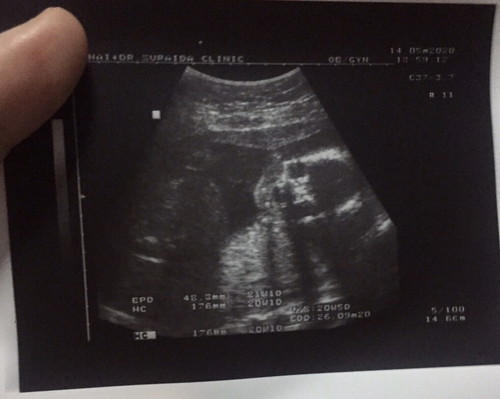

ทีมลูกสาวค่ะ กำหนดคลอด 26 กันยายน ? รอบนี้หันหน้ามาให้เห็นหน้าชัดๆๆ โครงรูปหน้าเหมือนพ่อมาก หนูจะออกมาได้พ่อเต็มๆเลยหรอลูก ??♥️

ทีมลูกสาวค่ะ 1 ก.ย. 63 ไม่ต้อง 4 มิติก็พอรู้ว่าหน้าจะเหมือนใคร 🤣🤣🤣